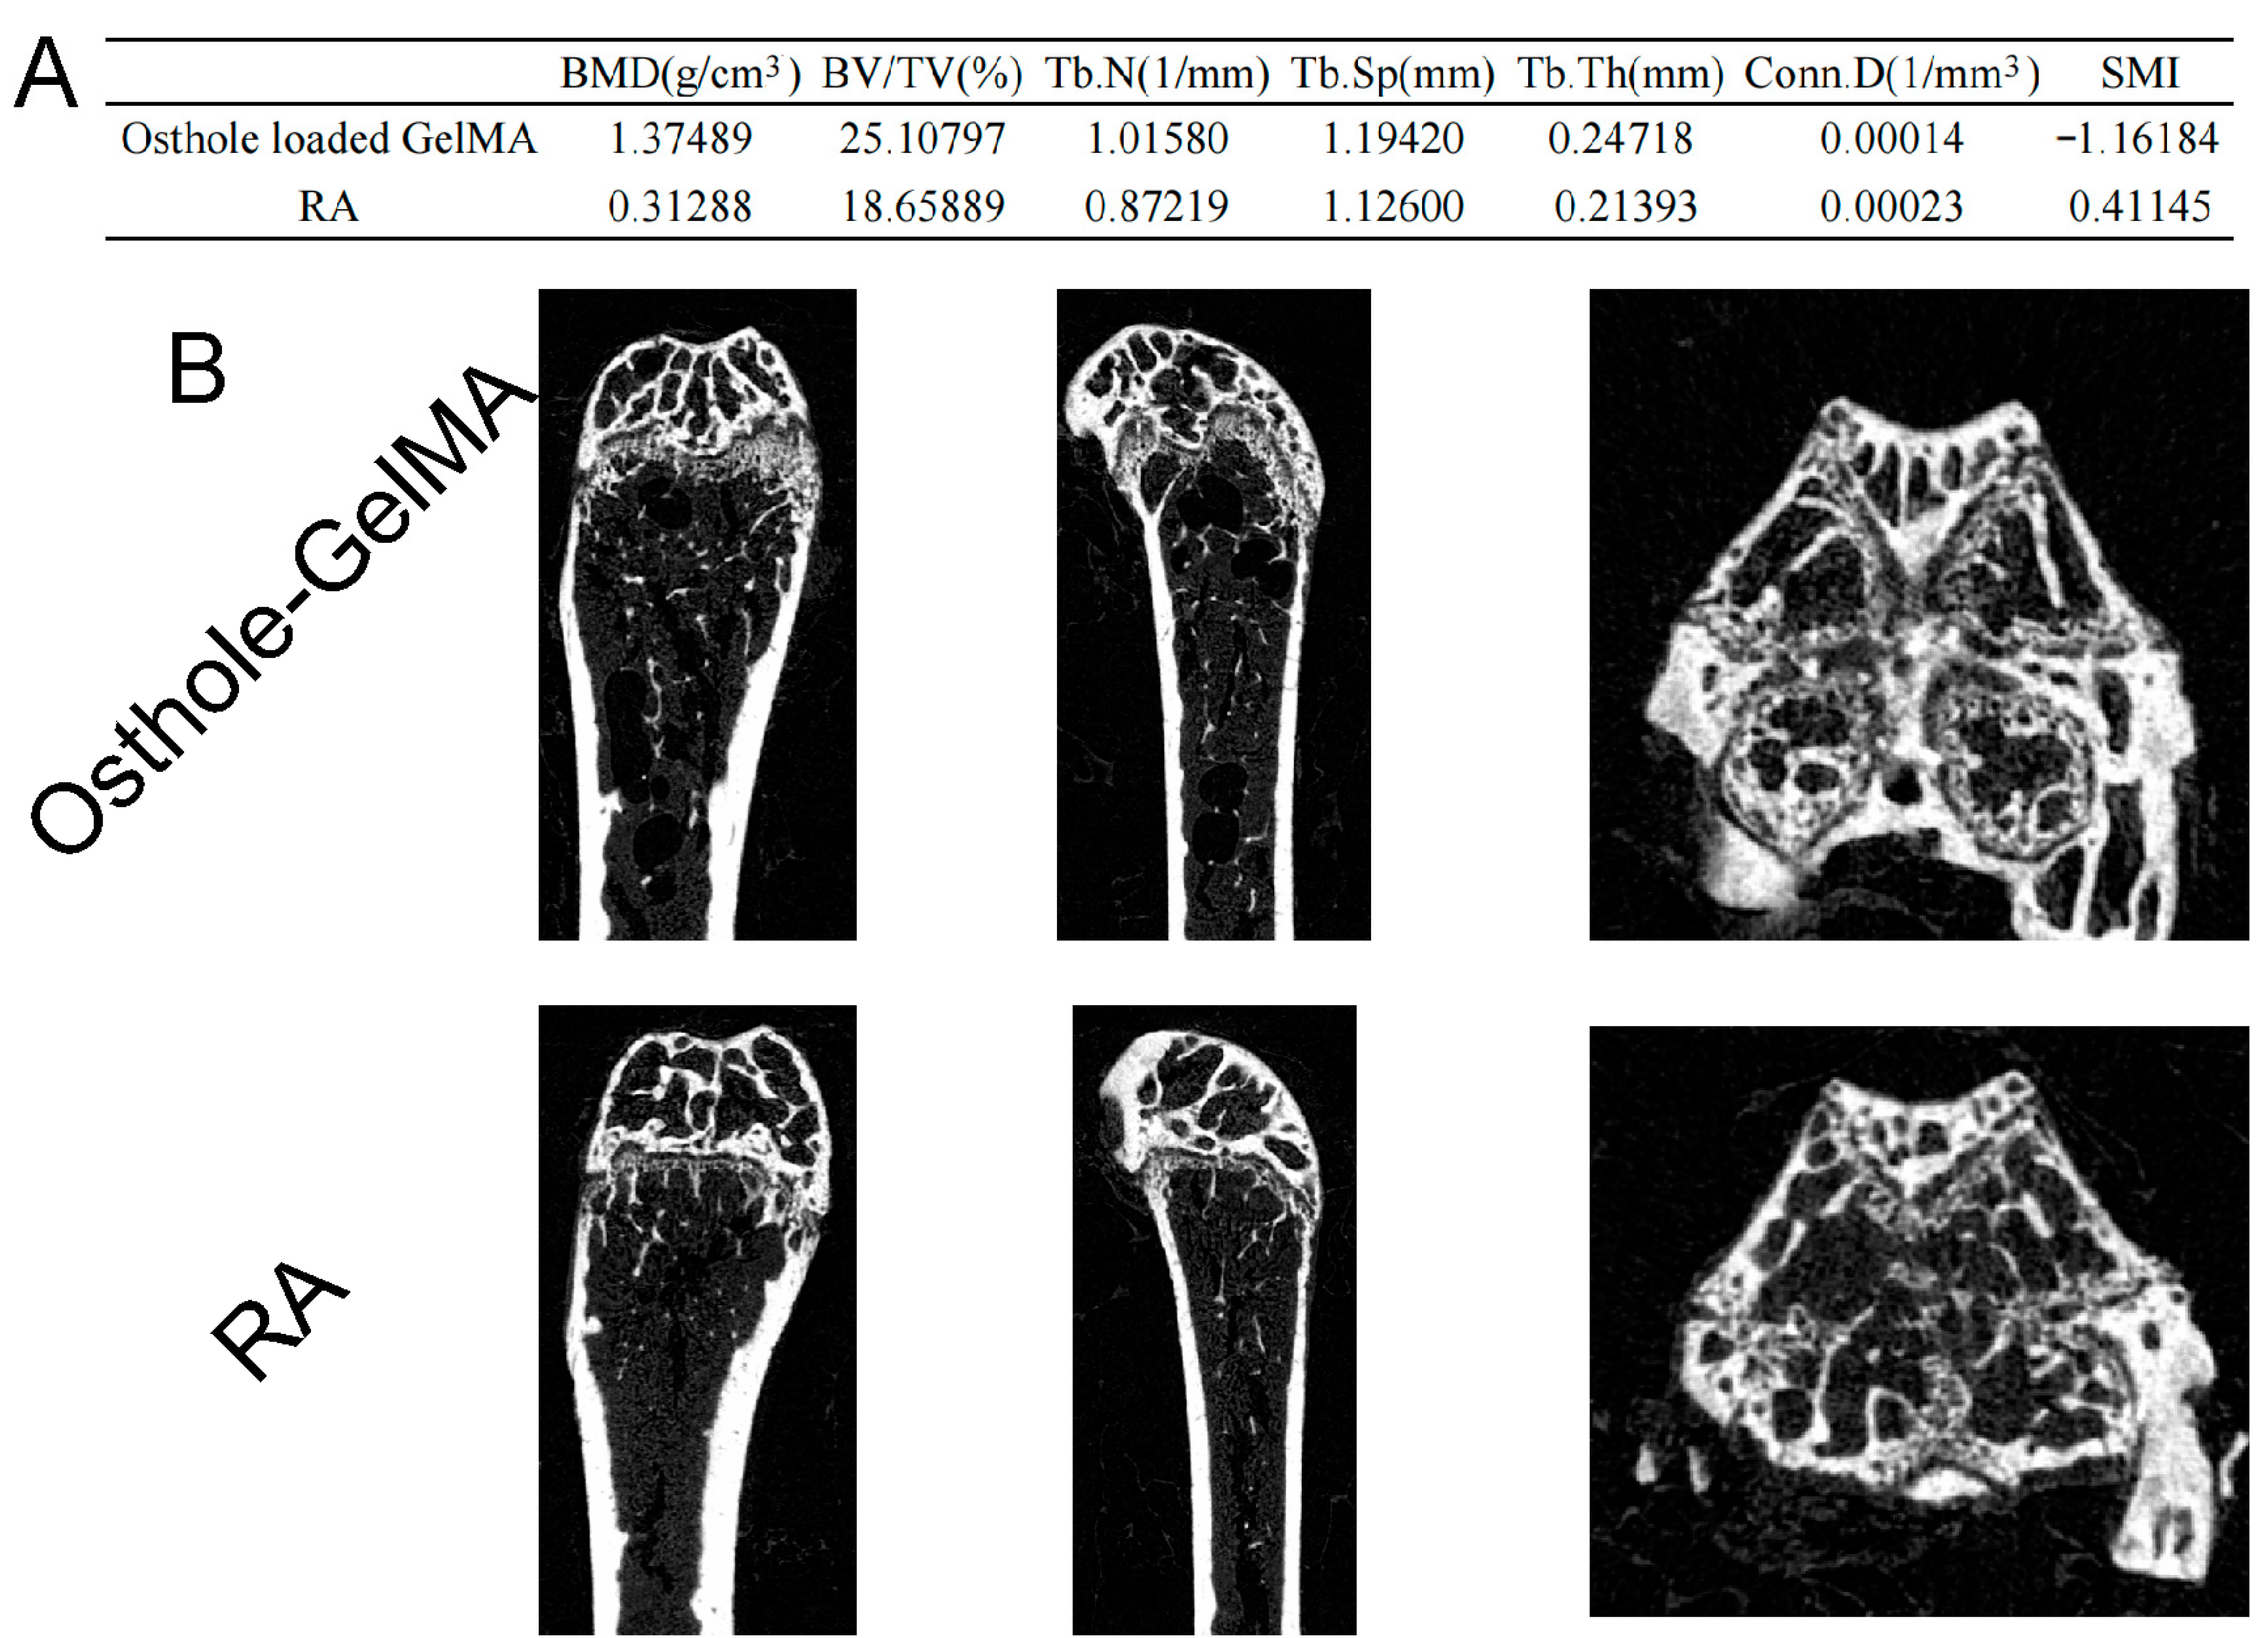

2.7. Effects of Osthole-Loaded GelMA in the Hip of CIA Mice Model